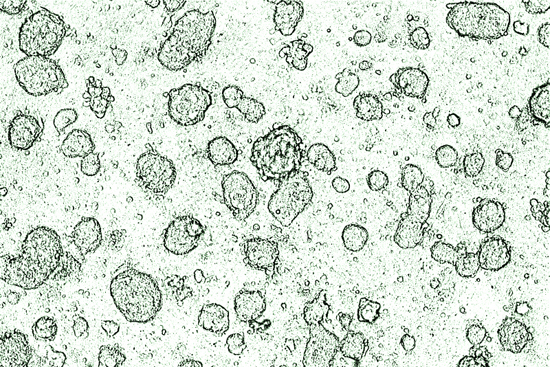

Murphy: It would be a problem. The injunction not only blocks expansion, it says original lines aren’t usable. An individual cell line comes from an individual embryo. Cells culled from that embryo are grown in Petri dishes and become an established human cell line, with all the functionality of adult tissue. Once the line is established, it can be expanded. It’s a long process, it’s immortal, and the lines are well tracked and carefully monitored.